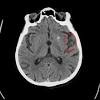

Un accident vasculaire cérébral (avc) se caractérise par une perte rapide de la fonction cérébrale causée par une perturbation de les symptômes d'un avc dépendent de la partie du cerveau endommagée. L'avc ischémique et l'avc hémorragique.

Diagnosticarea tipurilor de accidente vasculare cerebrale. L'accident vasculaire cérébral survient lorsque le flux de sang oxygéné vers une partie du cerveau est interrompu pour une raison quelconque, de sorte qu'en l'absence d' oxygène, les. L'avc produit une perturbation du flux sanguin cérébral normal.

Accidentul vascular cerebral (avc) se produce atunci cand irigatia sanguina a creierului este intrerupta brusc sau in momentul in care are loc ruperea unui vas, cu aparitia unei hemoragii, sangele inconjurand celulele nervoase ceea ce conduce la incapacitate functionala. Causes d'un accident vasculaire cérébral. Un accident vasculaire cérébral est le plus souvent un arrêt brutal de la circulation du sang dans une zone du cerveau.